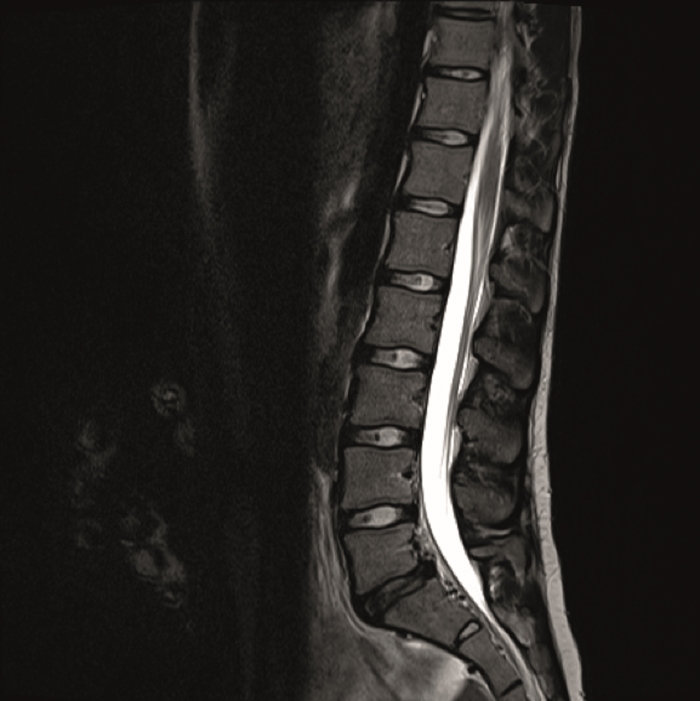

The preoperative standing image of the lumbar spine revealed a flat back with no obvious degeneration of the adjacent segment L1/L2 (Fig 6ab). The implants seemed regularly placed. After wide laminectomy, the spinal canal was open over the whole lumbar spine, illustrated on the MRI scan (Fig 6c).